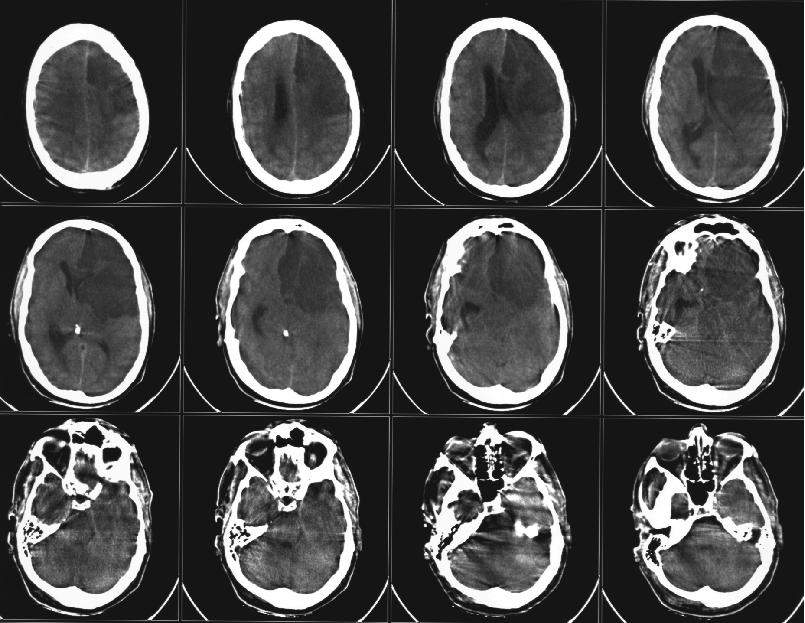

Фото: pictures.doccheck.com

Магнитно-резонансная томография, или МРТ, сегодня применяется для диагностики множества заболеваний — от артрита до рака. Точность диагностики напрямую зависит от качества изображения. Чтобы его повысить, нужно увеличивать время сканирования и напряженность поля томографов. Это требует больших затрат и снижает комфортность исследования. Люди с медицинскими имплантатами не могут проходить обследование на томографах с высокой напряженностью поля из-за опасности нагрева тканей в области имплантата и сбоев в его работе.

Ученые из Университета ИТМО совместно с коллегами из Нидерландов и Великобритании смогли решить эту проблему при помощи устройства на основе метаповерхности. Метаповерхность в данном случае представляет собой упорядоченную структуру из металлических резонаторов, размещенных в непроводящей среде. Эта структура способна перераспределить электромагнитное поле внутри томографа и сконцентрировать его вокруг себя. Если поместить ее под исследуемую часть тела, прием и передача локального сигнала улучшатся, а изображение станет более качественным.

«Обычно при МРТ обследовании все тело пациента облучают электромагнитным полем определенной мощности. Это ведет к тому, что во время сканирования значительный уровень поля создается в области конечностей, которые находятся максимально близко к источнику. В них может возникнуть нежелательный нагрев тканей, а это опасно для пациента, ─ рассказывает ведущий автор статьи Алена Щелокова, аспирант кафедры нанофотоники и метаматериалов Университета ИТМО. ─ Наши эксперименты показали, что использование метаповерхности позволяет увеличить эффективность катушки источника более чем в три раза. Это значит, что мы можем существенно снизить подаваемую мощность, но при этом обеспечить высокое качество изображения. Небольшая мощность позволяет сделать процедуру абсолютно безопасной для людей с имплантатами».